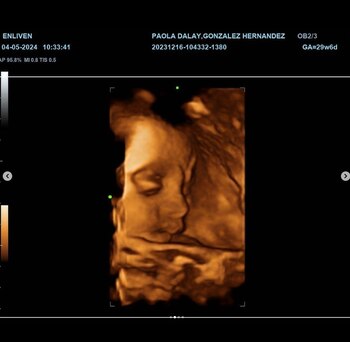

Recientemente, Dalay compartió tiernas imágenes del ultrasonido de su bebé, de quien ya conocen el sexo y a quien ya han nombrado Tessa, generando una oleada de comentarios y especulaciones sobre el parecido de la futura bebé con su famosa familia.

“Ya casi te conocemos Tessa, qué emoción”, escribió como descripción Paola Dalay, quien junto a emojis en forma de corazón mostró imágenes del más reciente ultrasonido que se realizó para conocer la evolución de la pequeña.

El nivel de interacción y expectativa de los seguidores de la pareja en redes sociales ha sido notable, especialmente ahora que se conoce el rostro de la nena, pues la publicación de las imágenes del ultrasonido generó gran cantidad de comentarios sobre a quién se parecerá Tessa.